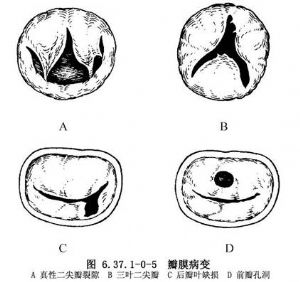

②瓣膜畸形:包括瓣叶裂隙、瓣叶缺如、交界处瓣膜发育不良或缺如、瓣叶孔洞。其中瓣叶裂隙在瓣膜畸形中最常见,以前瓣较多。裂隙形成可以是单纯的前瓣裂隙将二尖瓣前瓣分为两部分,而瓣下装置正常。也就是说二尖瓣口可能扩大,但乳头肌和交界位置正常。此类畸形又称为真性二尖瓣裂隙。另一类酷似房室隔缺损的二尖瓣裂隙,其特征是:三叶二尖瓣,瓣膜可以关闭良好;畸形不仅累及瓣叶,也累及乳头肌,如乳头肌移位,后瓣呈三角形和连接瓣环周径的1/4;瓣叶的关闭不全不一定是由于前瓣交界边缘对合不良,也可能是后外交界扩大。瓣叶组织缺如为局限的发育不良,常见于后瓣叶,缺损的游离缘无腱索或相连至细小的腱索。前瓣叶局限性缺损,常表现为孔洞(图6.37.1-0-5)。